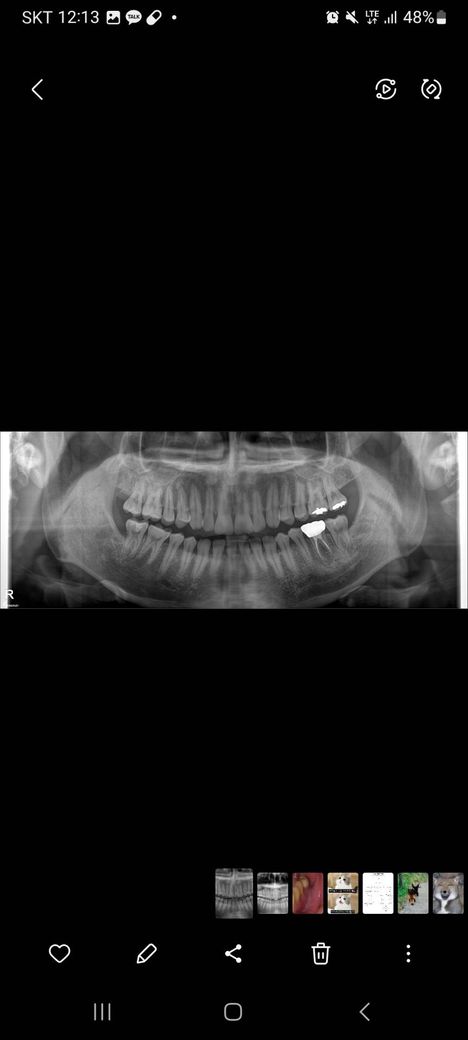

2대구치 충치 한번 봐주실 수 있을까요?

1번 사진이 최근에 찍은 사진, 2번 사진이 올해 6월에 찍은 사진입니다.

사진상 왼쪽 아래 2대구치 충치 한 번 봐주실 수 있을까요?

최근에 간 치과에서는 잇몸이 덮고있어서 충치 치료가 불가능하다고 하시고, 신경쪽까지 닿게되면 신경치료를 할 수도 있다고 하십니다.

혹시 정지 우식일 수 있을까요? 만약 아니라면 관리를 어떻게 하는 게 좋을까요?

신경치료를 해야할 정도의 상황으로 보이며 위치가 좋지 않아서 발치 가능성도 있어보입니다.

사랑니 때문에 생긴 충치 같습니다. 증상이 없으면 그냥 두시고 증상이 잇으면 신경치료를 하셔야될것같습니다.

47번 제2대구치의 경우 6개월 사이에 충치가 더 심하게 진행되거나 한 건 아니지만 애초에 충치가 너무 깊습니다. 이미 간접적으로 치수는 노출되었을 것 같습니다. 증상있으면 바로 신경치료 해야 하는 상황입니다.